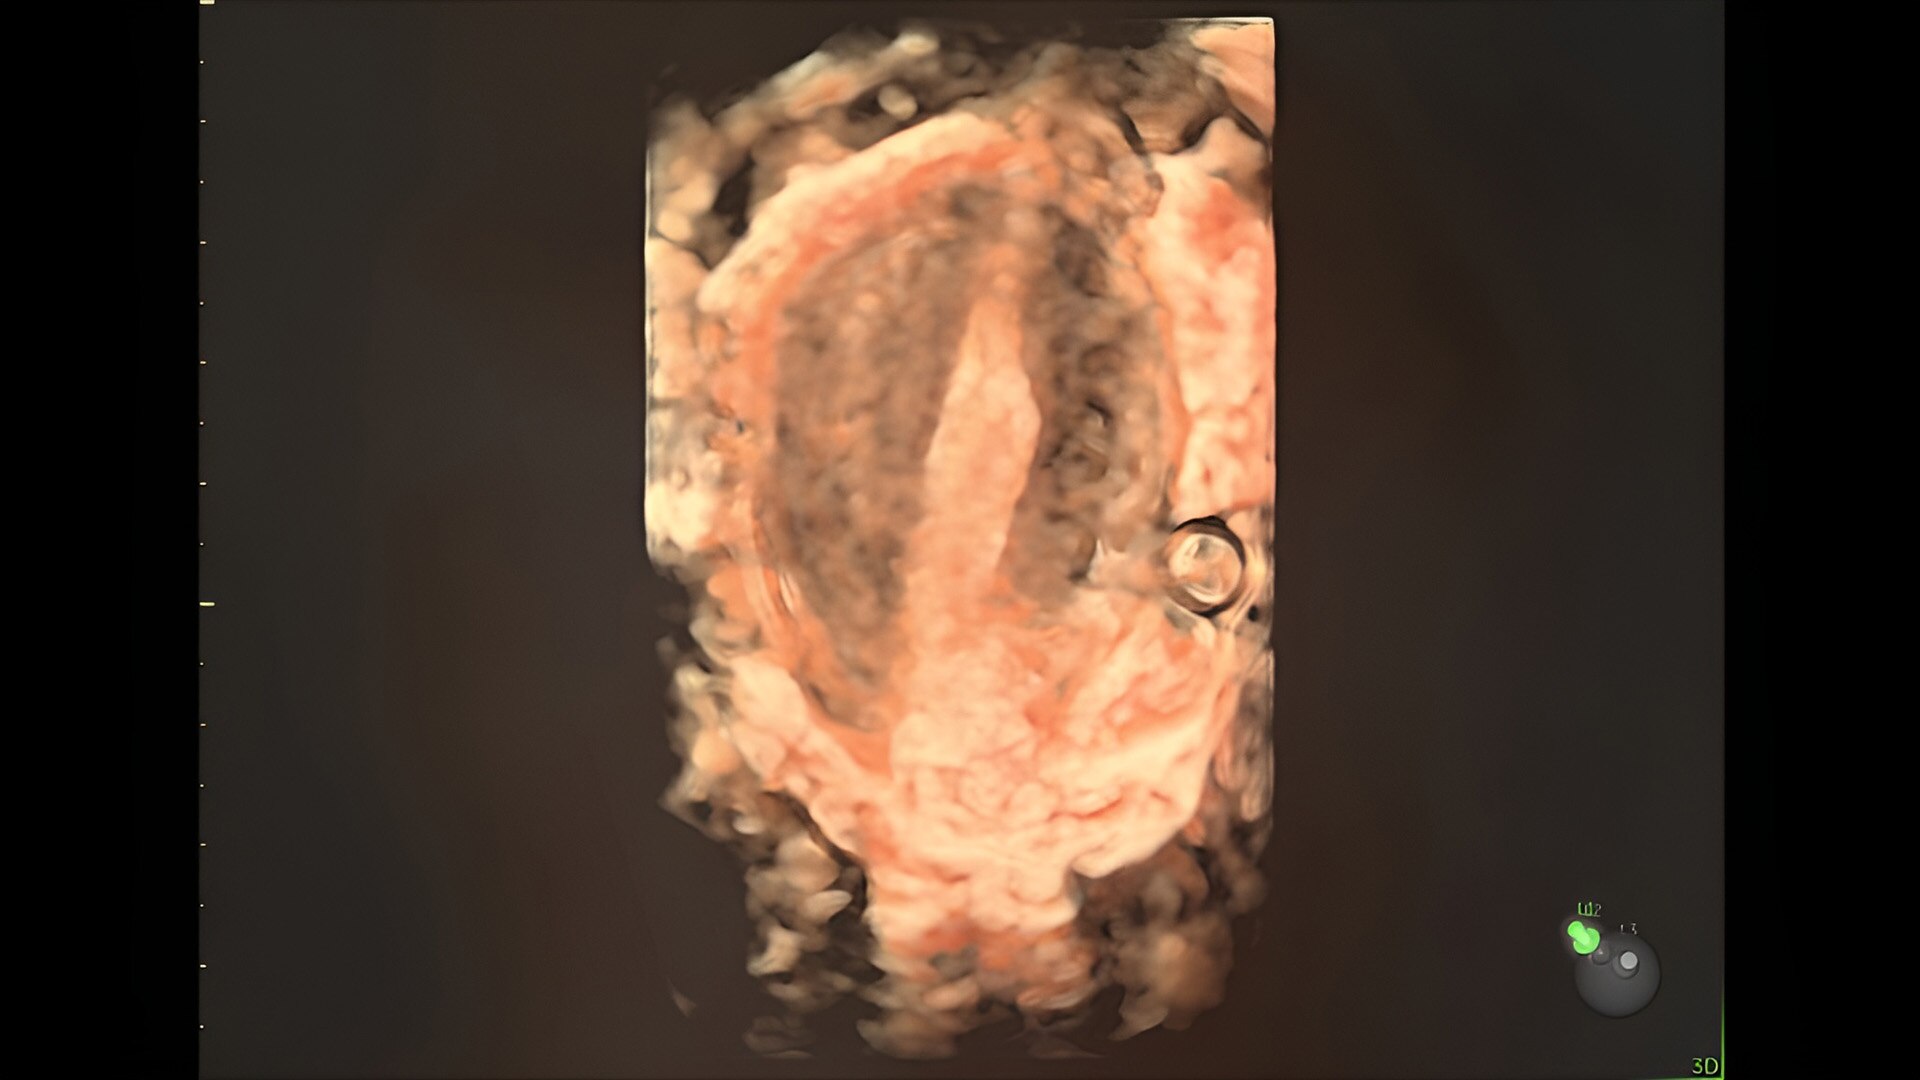

Fetal heart assessment

Detect, diagnose, and monitor with confidence using Radiant and fetalHQ

Identifying fetal cardiac abnormalities earlier means you can intervene sooner, plan for delivery, and potentially improve outcomes. The Voluson Expert 22 provides a full solution of progressive tools, to help distinguish the tiniest structures with stunning clarity to provide patient answers faster.